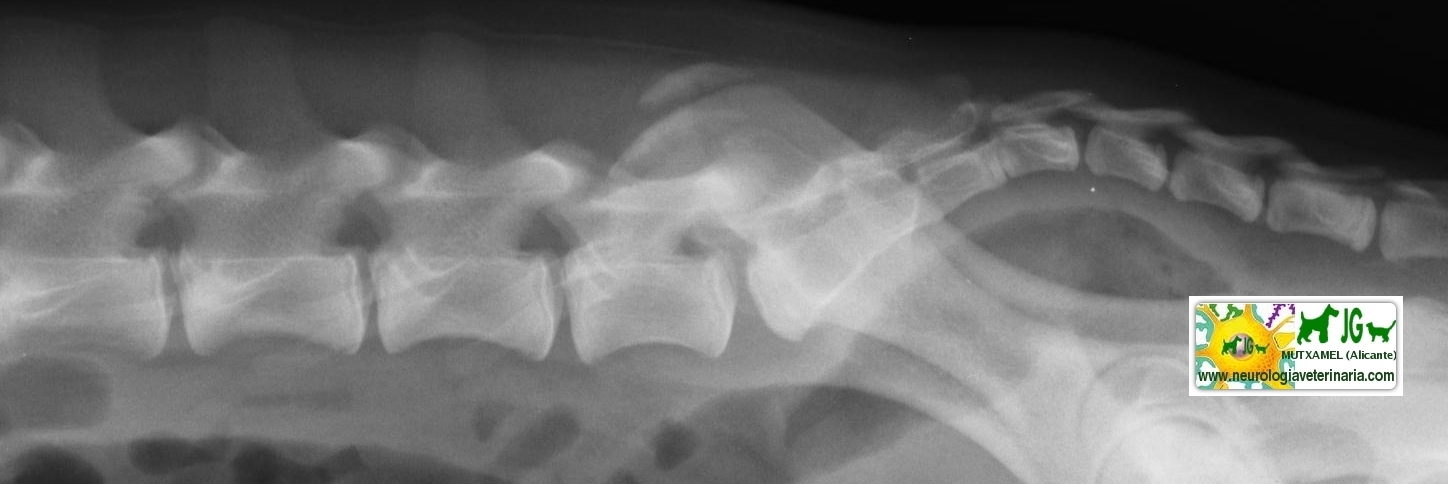

Radiografía con contrastes: mielografía por saco dural | |||||||||

![]() por Juan M. Griñán. Veterinario ![]() comparativa entre una mielografía (mostrando la aguja) y una resonancia magnética, secuencia SE T1w (mostrando donde está el saco dural, sitio para la inyección del contraste). Nótese la extravasación del contraste yodado en la mielografía. | |||||||||